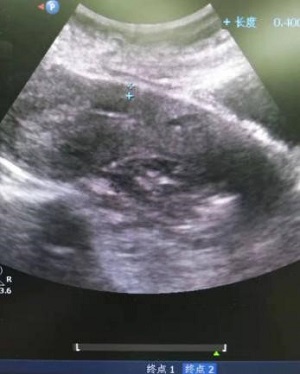

34岁的欧女士来自安仁县,因“停经55天,阴道流血4天,发现切口妊娠2天”于8月22日由门诊以“切口妊娠”收住入院。B超检查提示,剖腹产切口处15x14x11mm孕囊,内见卵黄囊,距离子宫浆膜层4mm,血流丰富。考虑切口妊娠。MRI提示:子宫中段前壁见切口凹陷,有26x15mm大小孕囊附着,附着处16mm肌层变薄,最薄处4mm,子宫前壁与腹壁粘连。诊断:子宫切口妊娠,子宫前壁与腹壁粘连。

超声像                                       MRI影像